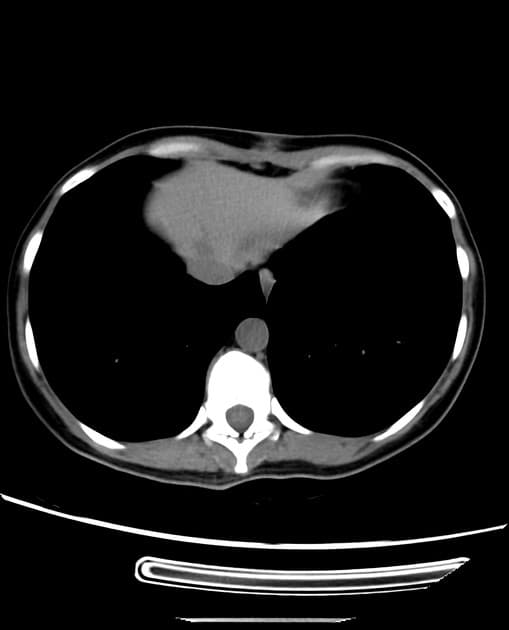

- Tổn thương dạng thùy (lobulated) kích thước 35 x 45 mm nằm ở phân đoạn V của thuỳ phải, liền kề với túi mật (gallbladder).

- Tổn thương này tăng tín hiệu (hyperintense) trên hình ảnh T2-weighted MRI.

- Trên hình ảnh cộng hưởng từ có tiêm thuốc tương phản động (dynamic contrast-enhanced imaging), thấy tăng quang dạng nốt (nodular) ở vùng ngoài viền (peripheral) ban đầu, tiếp theo là quá trình lấp đầy dần từ ngoài vào trong (slow centripetal filling).

Hình ảnh cộng hưởng từ (MRI) phù hợp điển hình với u sợi mạch gan (hepatic hemangioma).

- "U sợi mạch gan thường biểu hiện tăng tín hiệu T2 và tăng quang dạng nốt ở viền ngoài với quá trình lấp đầy từ từ từ ngoài vào trong trên cộng hưởng từ có tiêm thuốc tương phản động."

U sợi mạch gan là khối u gan lành tính phổ biến nhất, thường được phát hiện tình cờ trên hình ảnh học. Bệnh xuất phát từ các mạch máu bất thường và gồm các khoang giãn chứa đầy máu được lót bởi tế bào nội mô. Trên cộng hưởng từ (MRI), hình ảnh điển hình bao gồm tăng tín hiệu rõ rệt trên T2 và kiểu tăng quang dạng nốt ở vùng ngoại vi trong thì động mạch, tiếp theo là quá trình lấp đầy dần từ ngoài vào trong ở các thì muộn. Dấu ấn hình ảnh này rất đặc hiệu, cho phép chẩn đoán chắc chắn không xâm lấn trong hầu hết các trường hợp. Mặc dù có thể sinh thiết, nhưng thủ thuật này tiềm ẩn nguy cơ chảy máu và thường được tránh. Điều trị mang tính bảo tồn, không cần cắt bỏ hay theo dõi định kỳ trong các trường hợp điển hình, trừ khi có nghi ngờ chẩn đoán hoặc bệnh nhân có triệu chứng.